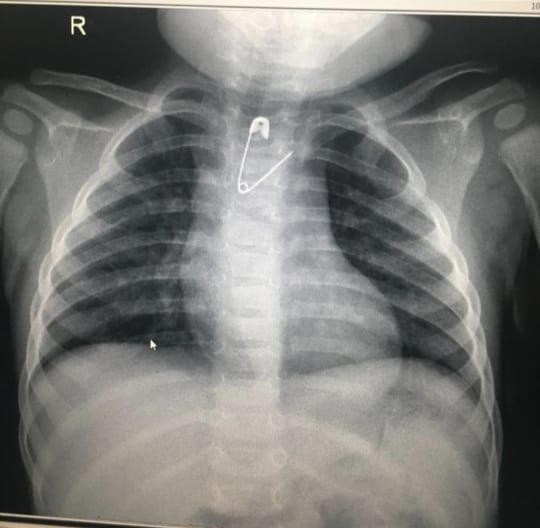

تمكَّن فريق طبي بمستشفى الولادة والأطفال عضو التجمع الصحي بمكة المكرمة من إنقاذ طفلة بعمر 8 شهور بإزالة مشبك مفتوح عن طريق المناظير دون إجراء إي تدخل جراحي.

وقاد العملية الدكتور علي الشمراني وطبيب التخدير د.أنس بركات، حيث أوضح د. الشمراني  قائلاً : أن مثل هذه الحالات تعد نادرة وذلك لصغر عمر الطفلة وتعتبر هذه الطفلة الأولى التي يستخرج منها هذا الجسم الغريب (المشبك) على مستوى المنطقة بعمر لم يتجاوز 8 أشهر من الجزء العلوي بالمريء, كما نوه بالتعاون البناء بين الأقسام المختلفة ومنها الأشعة والتخدير في علاج المرضى.